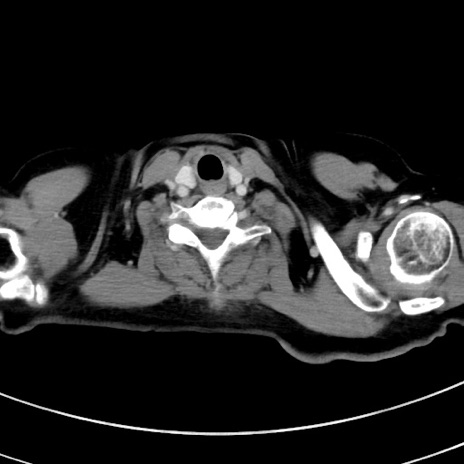

冠状断像

【症例】 60歳代女性

【主訴】むかつき、みぞおちの痛み

【現病歴】3日前よりむかつきがあり、食事がとれない。

【既往歴】糖尿病

【身体所見】発熱なし、心窩部圧痛軽度あるも、腹膜刺激症状なし。

【データ】WBC 7400、CRP 1.92